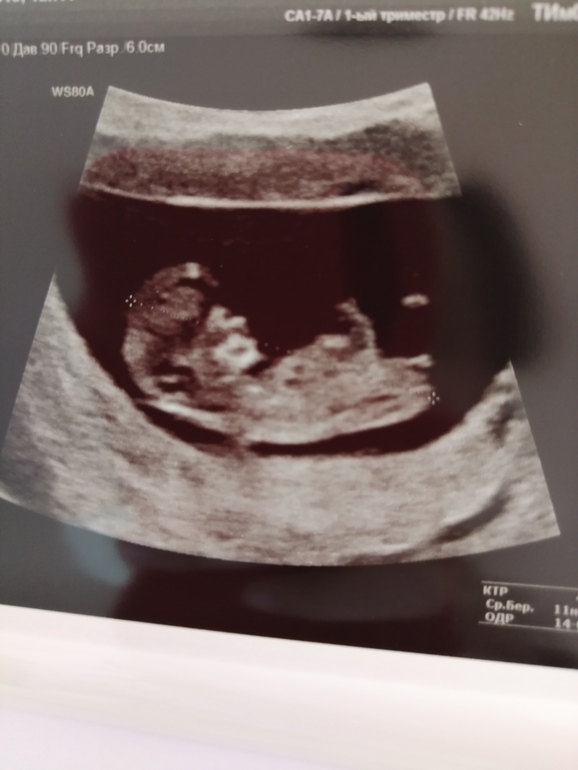

Немного не доросли☺️ 42 мм, 11 недель ровно)) в общем по месячными разница в неделю, но это не удивительно, так как какой был цикл непонятно, и о была однозначно поздняя))

Сейчас все хорошо, твп пока не информативно, носик есть, сейчас по сроку прериканий нет, чему я очень рада!!!

Так там прыгал, такой сладенький)) 😍

Ну и фото крошечки нашей)

Лежит удобненько так💖💖💖